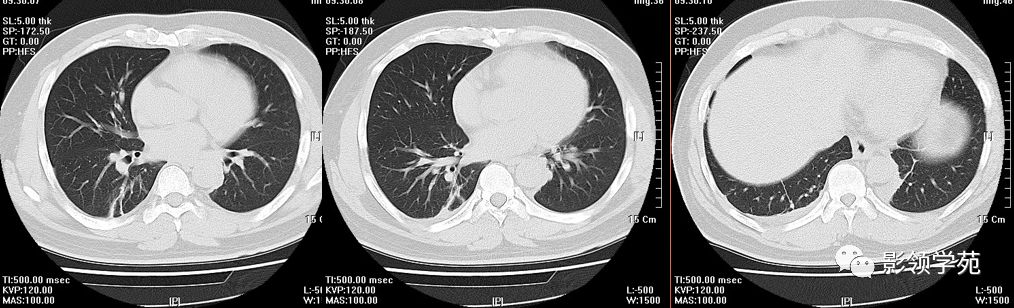

患者刘某,男,56岁,摔伤致左侧3~9肋骨骨折,左肺挫伤,左侧胸腔大量

图片尺寸2000x2667